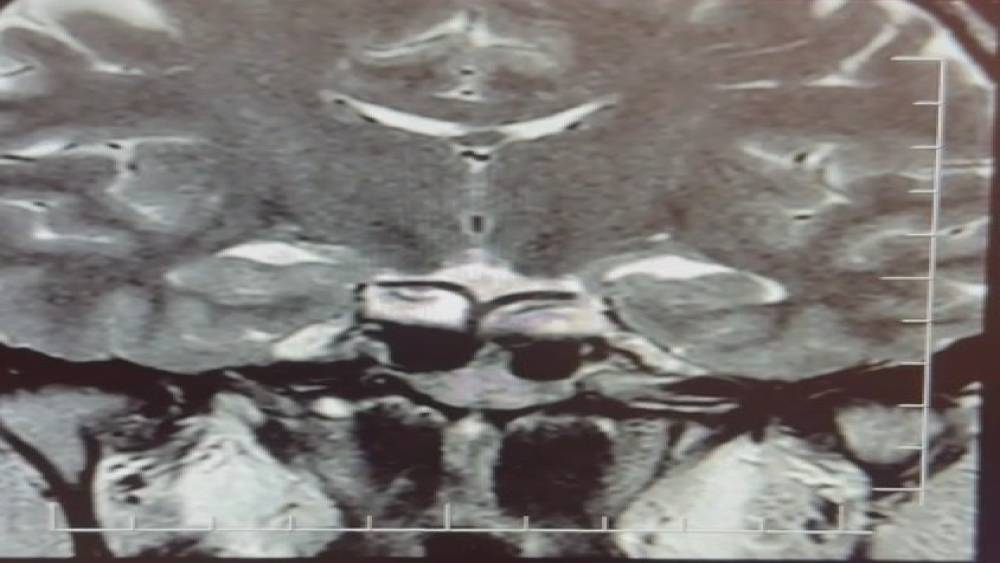

Yapılan ileri tetkiklerde hastaya hipofiz MR çekildiğini aktaran Çiftçoğlu, "MR sonucunda beynin hipofiz bölgesinde ‘prolaktinoma’ olarak adlandırılan bir tümör tespit ettik. Bu tümör, prolaktin hormonunun aşırı salgılanmasına neden oluyor. Genellikle iyi huylu olup ilaç tedavisiyle kontrol altına alınabiliyor" diye konuştu.